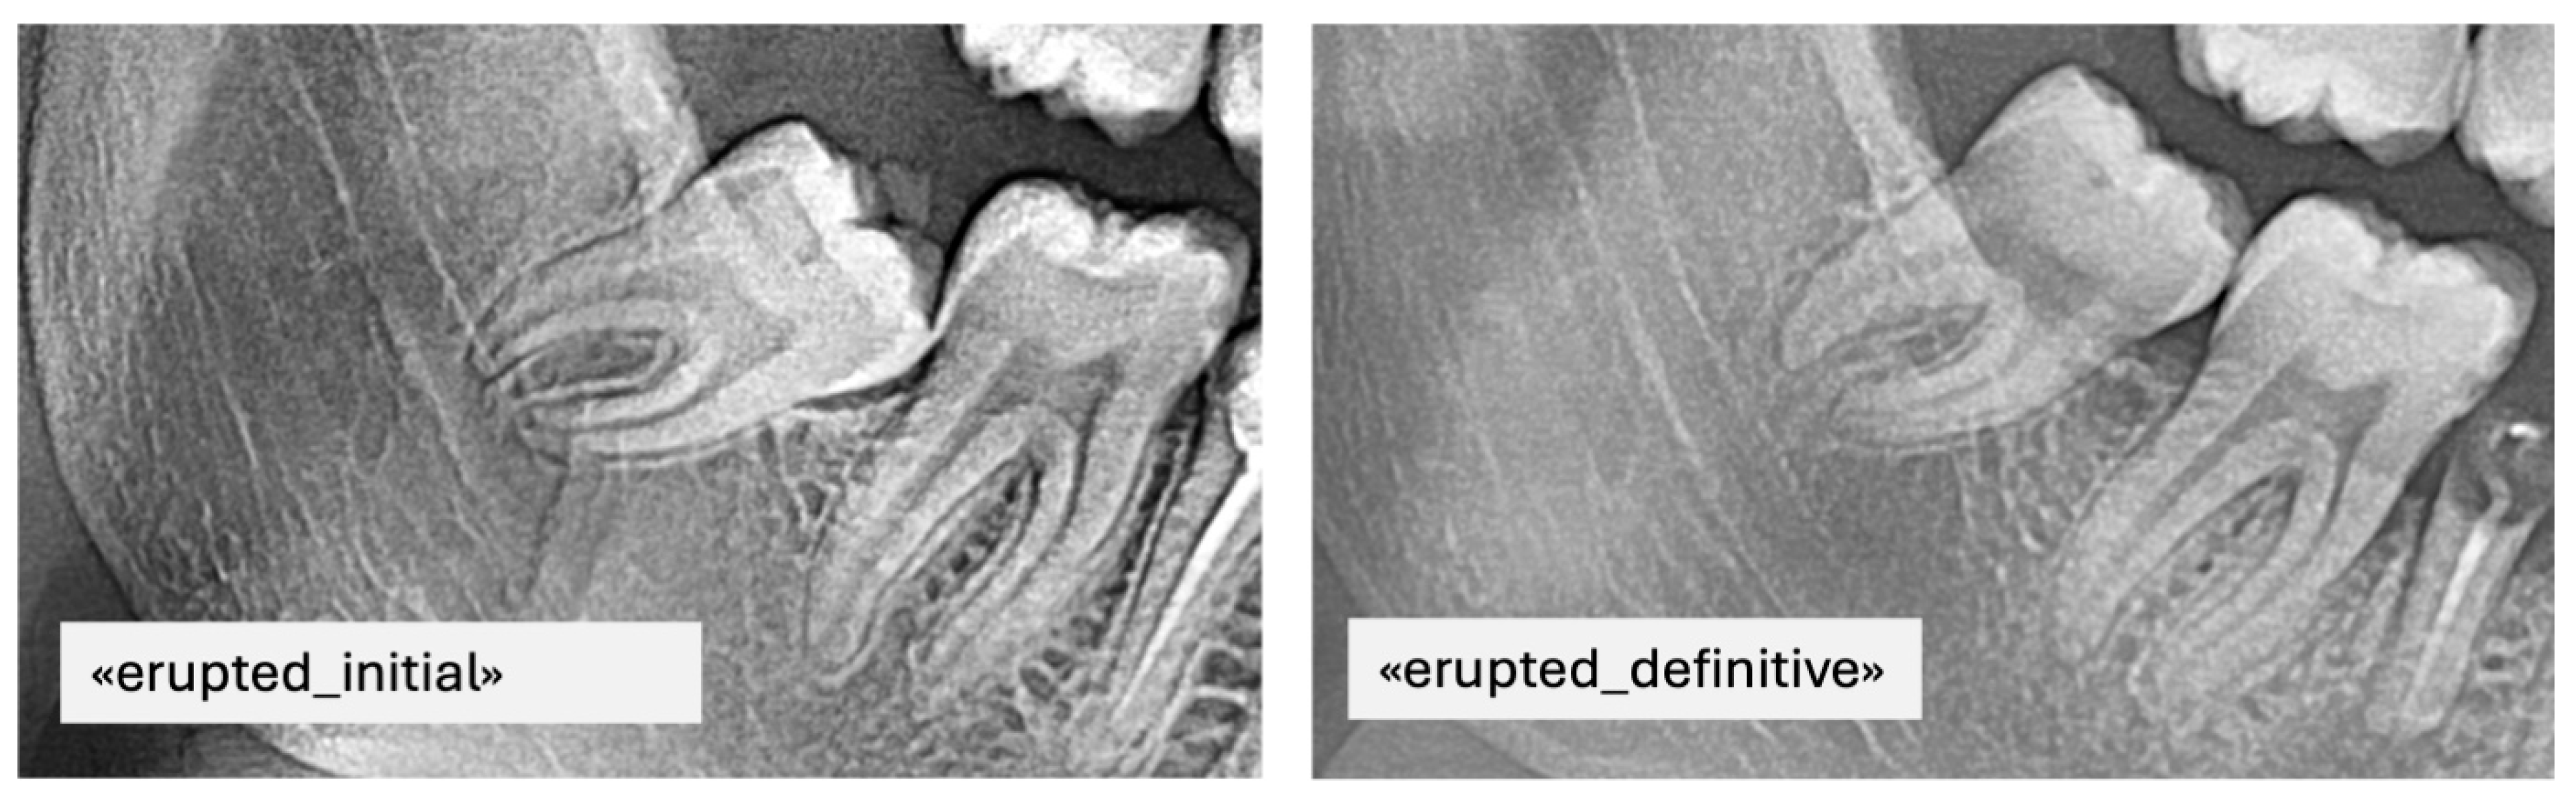

- Erupted: the occlusal surface of the third molar was at or above the occlusal plane of the adjacent second molar, with no overlying bone visible radiographically.

- Partially impacted: the occlusal surface was below the occlusal plane but partially exposed, with part of the crown still covered by alveolar bone or showing limited eruption space between the distal of the second molar and the anterior border of the ramus.

- Impacted: the third molar was entirely below the occlusal plane, with full bone coverage and/or evident spatial limitation or unfavorable angulation (e.g., mesioangular or horizontal position) in relation to the second molar.